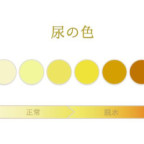

おしっこが透明な人は…